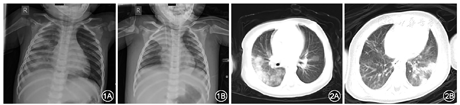

影像学检查:入院当日患儿胸部X线片示右上肺及右下肺大片模糊影(图1A),肺部CT示两肺纹理增强、右肺可见大片实变影为主,伴磨玻璃影(图2A)。B超示双肾积水,双肾稍饱满,实质回声稍增强,下腔静脉塌陷。

诊疗经过:入重症隔离病房后立即予以补充血容量、纠正酸中毒、多巴胺静脉持续注射以改善循环,并予气管插管(气管插管内可见淡血性分泌物)呼吸机辅助通气[模式为压力控制通气,呼吸频率40次/min,吸入氧浓度(fraction of inspiration O2,FiO2)0.95,呼气末正压10 cmH2O(1 cmH2O=0.098 kPa),吸气峰压33 cmH2O,吸呼比1.0∶1.5],干扰素α-1b雾化,丙种球蛋白(400 mg/kg×5 d)及甲泼尼龙静脉滴注(2 mg/kg×3 d),予抗感染(美罗培南、利奈唑胺、奥司他韦)及胃肠减压等对症支持治疗。1月27日凌晨5时复查动脉血气分析示pH 7.12,PaCO2 40.4 mmHg,PaO2 88 mmHg,SaO2 0.931,碳酸氢根12.5 mmol/L,剩余碱-15 mmol/L,乳酸0.2 mmol/L。患儿经皮氧饱和度维持在0.90左右(PaO2/FiO2=93 mmHg,氧合指数=19),予间断俯卧位通气治疗。1月27日9时患儿仍无尿,肢端冰凉,于11点行连续血液净化治疗。经治疗后,1月29日患儿氧合明显改善(PaO2/FiO2=212 mmHg,氧合指数=7.1),入院第6天复查床旁X线片示两肺通气改善,右下叶及左上叶肺炎部分吸收,右上叶肺不张(图1B)。入院第10天患儿病情明显好转,氧饱和度维持在0.95以上,尿量为1 080 ml,双侧呼吸运动对称,双肺可闻及少量湿啰音,行脑电图检查提示背景活动为弥漫性慢波,经撤机评估后,予成功撤离呼吸机。入院第11天复查肺部CT示右肺病灶明显改善,左肺病灶有所进展(图2B)。继续予抗感染等对症治疗,至2月8日,患儿无发热,偶有咳嗽,无腹泻、呕吐,鼻导管吸氧(1 L/min)下生命体征平稳。